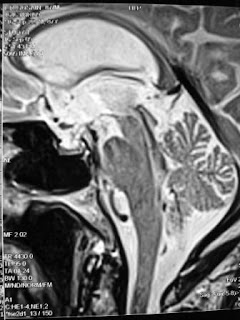

87 years old male with Gradually worsening bladder symptoms—unable to hold urine, Emotional lability,Occasional falls-unsteadiness while walking since last 10 months

Diagnosis: Normal Pressure hydrocephalus

Findings: Triventricular dilatation out of proportion to atrophy with periaqueductal hyperintensity, large jet of flow void in the aqueduct and fourth ventricle, periventricular hyperintensity, upward ballooning of corpus callosum, posterior gyri opposed aginst the calvarium, CSf pocket in medial sulcus

Pre CSF tap CSF flow study result through aqueduct shows peak veocity of 16.92cm/sec and stroke volume of 111 mirolt/sec while post CSF tap (70 ml) CSF flow study sows peak velocity of 7.79 cm/sec and stroke volume of 8 microlt/sec.